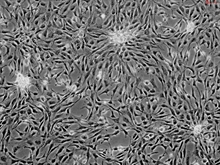

Human Cardiac Myocytes

Cardiac myocytes are the most physically energetic cells in the body. They are highly specialized high-oxygen-content cells that house a large number of mitochondria. They occupy as much as 75% of the cardiac mass, but constitute only about one third of the total cell number in the heart. Differentiated cardiac myocytes have little capacity to proliferate; however, hypertrophic growth has been shown to respond to alpha1-adrenergic stimuli via the Ras/MEK pathway. All cardiac myocytes are capable of spontaneous rhythmic depolarization and repolarization of their membranes. Contraction of cardiac myocytes is myogenic, which is independent of nervous stimulation. There is a complex network of signals in cardiac myocytes regulating the rhythmic pumping of the heart. Cardiac myocyte hypertrophy and apoptosis have been implicated in the loss of contractile function during heart failure. (SC6200)